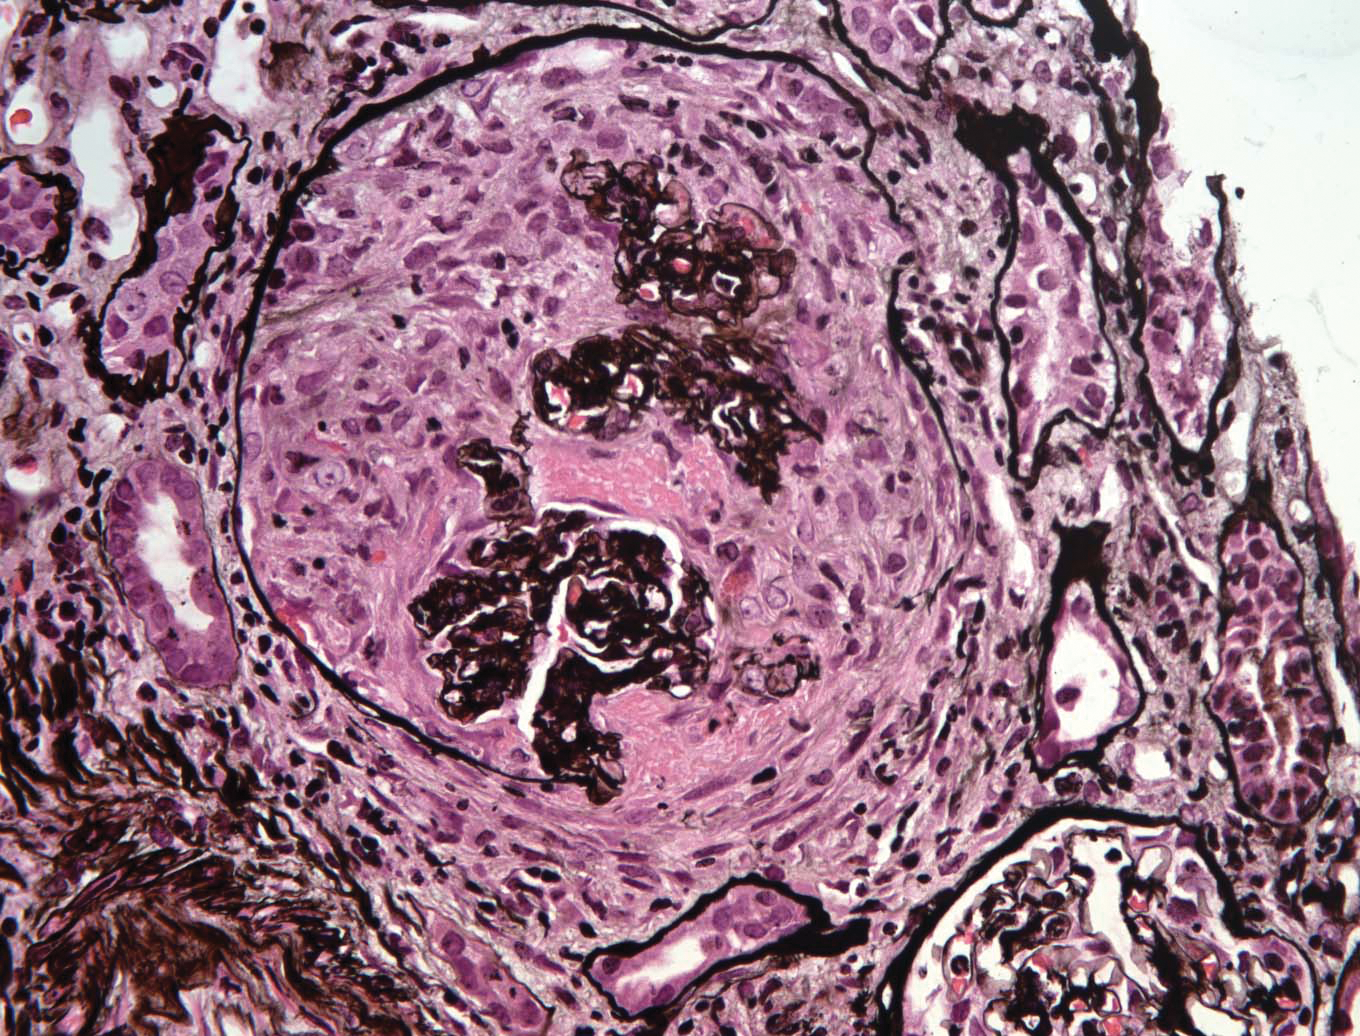

9b70fea5-1079-4abc-a0df-, Heptinstall's Pathology of the Kidney: 9781451144116,

Heptinstall's Pathology of the Kidney: 9781451144116, Heptinstall's Pathology of the Kidney: 9781451144116,

Heptinstall's Pathology of the Kidney: 9781451144116, Heptinstall's Pathology of the Kidney: 9781451144116,

Heptinstall's Pathology of the Kidney: 9781451144116, Renal Pathology of Ciliopathies - Thivya Sekar, Neil J,

Renal Pathology of Ciliopathies - Thivya Sekar, Neil J, Heptinstall's Pathology of the Kidney: 9781975161538,

Heptinstall's Pathology of the Kidney: 9781975161538, Non-neoplastic renal diseases (Chapter 31) - Silverberg's,

Tubulointerstitial Diseases (Chapter 12) - Silva's, Diagnostic Pathology: Kidney Diseases: 9780443107177

Diagnostic Pathology: Kidney Diseases: 9780443107177